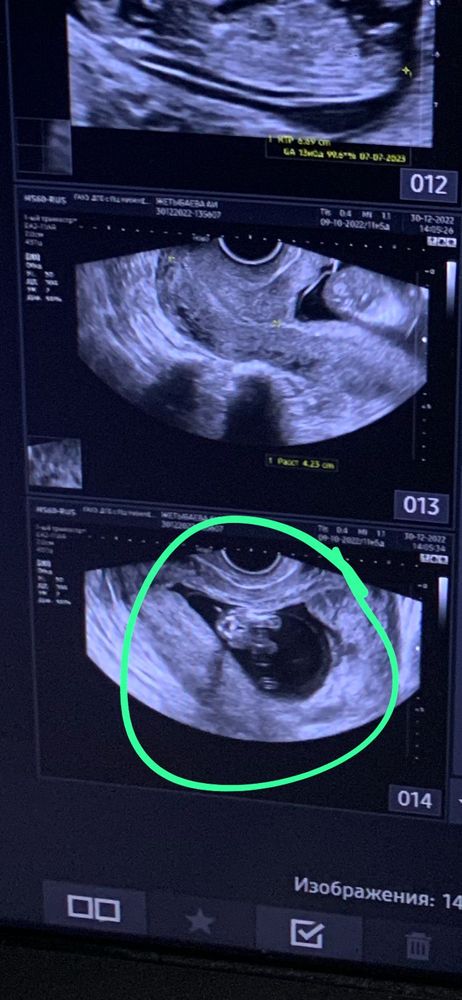

Кто будет?) кто разбирается?) 13 недель на фото)

В 13 недель так пол смотреть неверно. И у мальчиков и у девочек здесь половой бугорок. Смотрят сбоку и замеряют угол между бугорком и спинкой. А в таком положении у любого пола будет так торчать

Анастасия , по верхнему снимку, если это половой бугорок - девочка

Похоже на девчонку. У мальчиков обычно бугорок загнут наверх) Но точно определит конечно узист немного позже. Вообще конечно странно, что не сказали, если врач опытный то по такой четкой картинке понял бы пол.

В 13 неделек смотрят ещё сбоку малыша, а не между ножек) По самому верхнему снимку похоже на девочку по половому бугорку(если это он)) на скрининге предположили пол?)